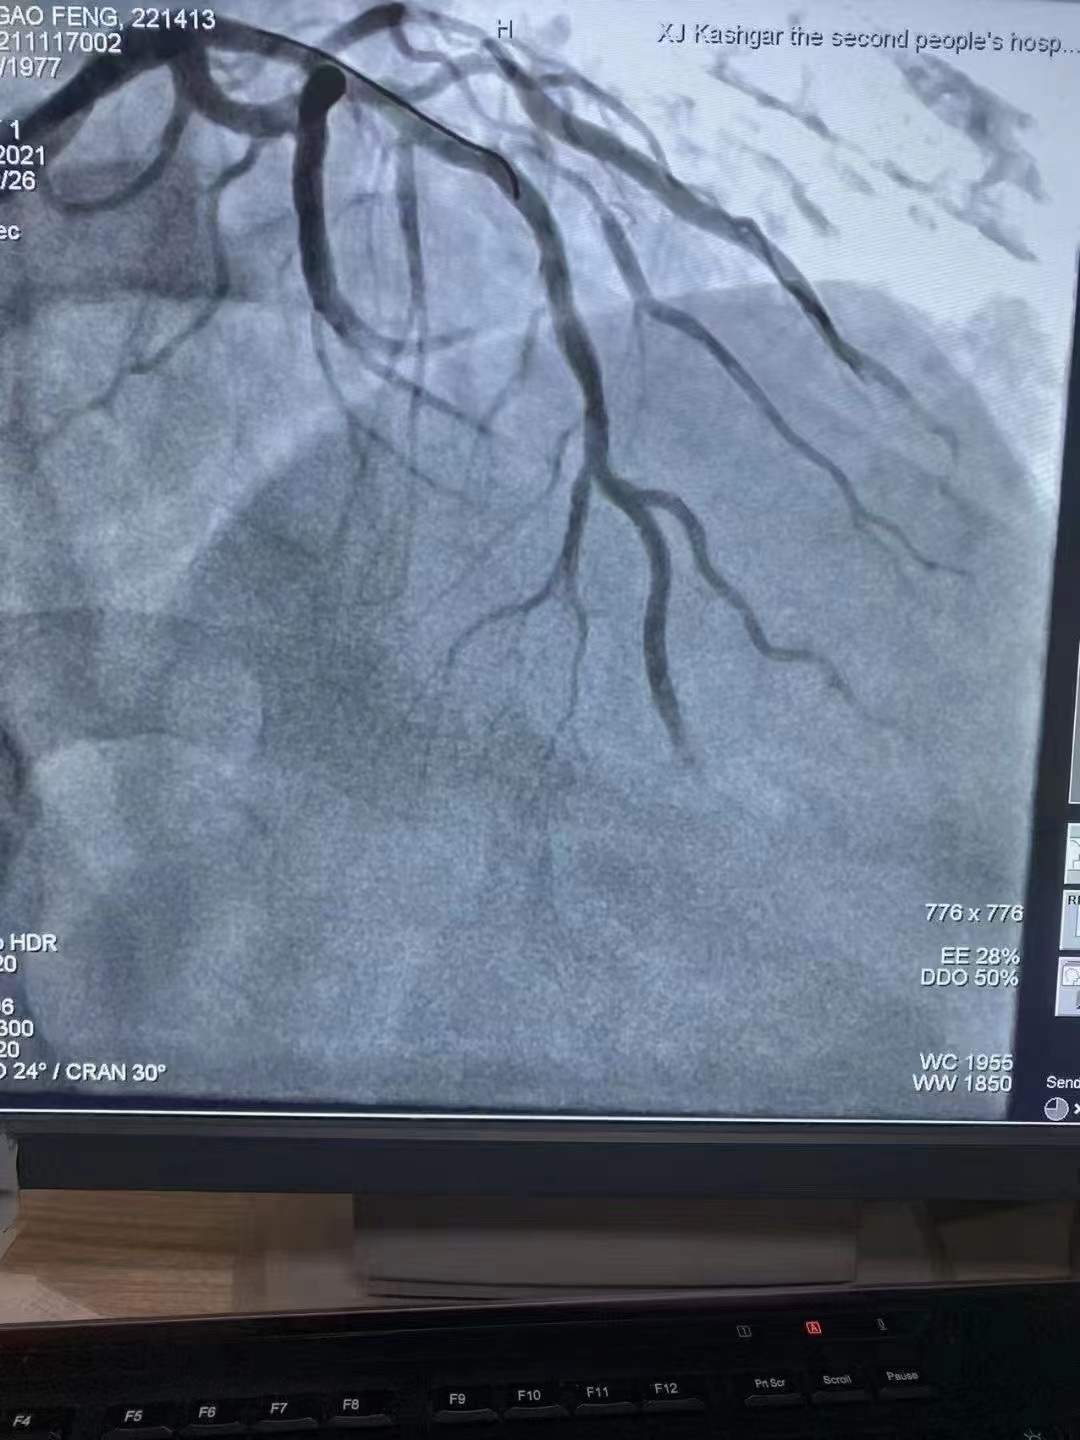

完美修復心歸自然情系邊疆

祝賀 新疆喀什地區第二人民醫院心內科在復旦大學中山醫院援疆專家姚志峰主任帶領下成功為患者植入新疆首例Xinsorb生物可吸收支架,感謝援疆項目的扎實落地,溫暖了新疆各族百姓Xinsorb與白衣天使共同守護每一個心臟!